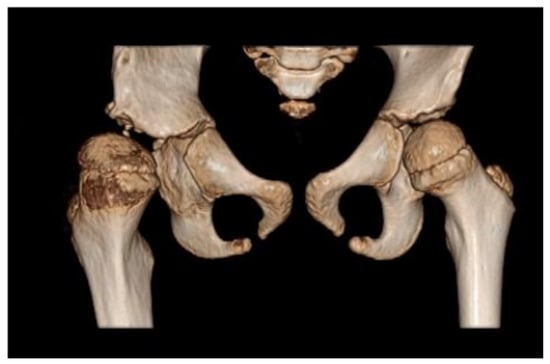

Due to persistent radiological evidence of subluxation in the right hip joint, at the age of 4.5, another pelvis osteotomy was performed using the Salter method. At the age of five, all metallic osteosyntheses were surgically removed and a pelvic computed tomography (CT) scan was performed (Figure 4). The next (third) surgery involving varus direction and de-rotative osteotomy on the proximal part of the right femur was performed on the girl at age 6 (Figure 5).

Figure 4. Computed tomography (CT) of the pelvis—3D scan carried out at 5 years of age. The relative tilt angle of the femoral head is about 47°; the angle of internal rotation is about 25°. Knee set in internal rotation. Femoral head in anterolateral subluxation. Joint space significantly widened. Thickening of soft tissues around the hip joint; exudate cannot be excluded. Differentiation reveals postoperative changes and inflammation. The acetabulum is slightly distorted in the area of the roof and flattened with irregular contours, marginal sclerotization, and small defects. A ~4 mm calcification or ossification can be seen in the soft tissues in front of the anterior part of the acetabular roof and below the posterior edge of the roof. The femoral head is flattened. There is marked thinning of the bone structure of the femoral head and neck.